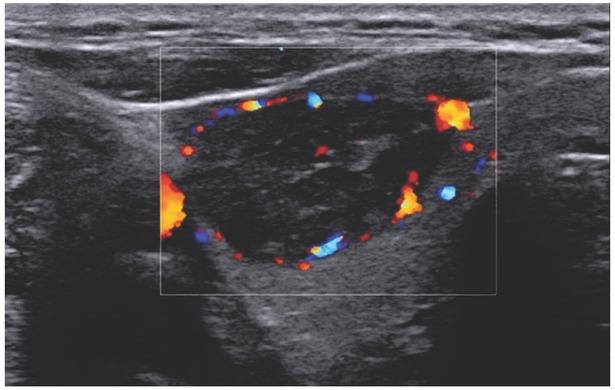

Fig. 4